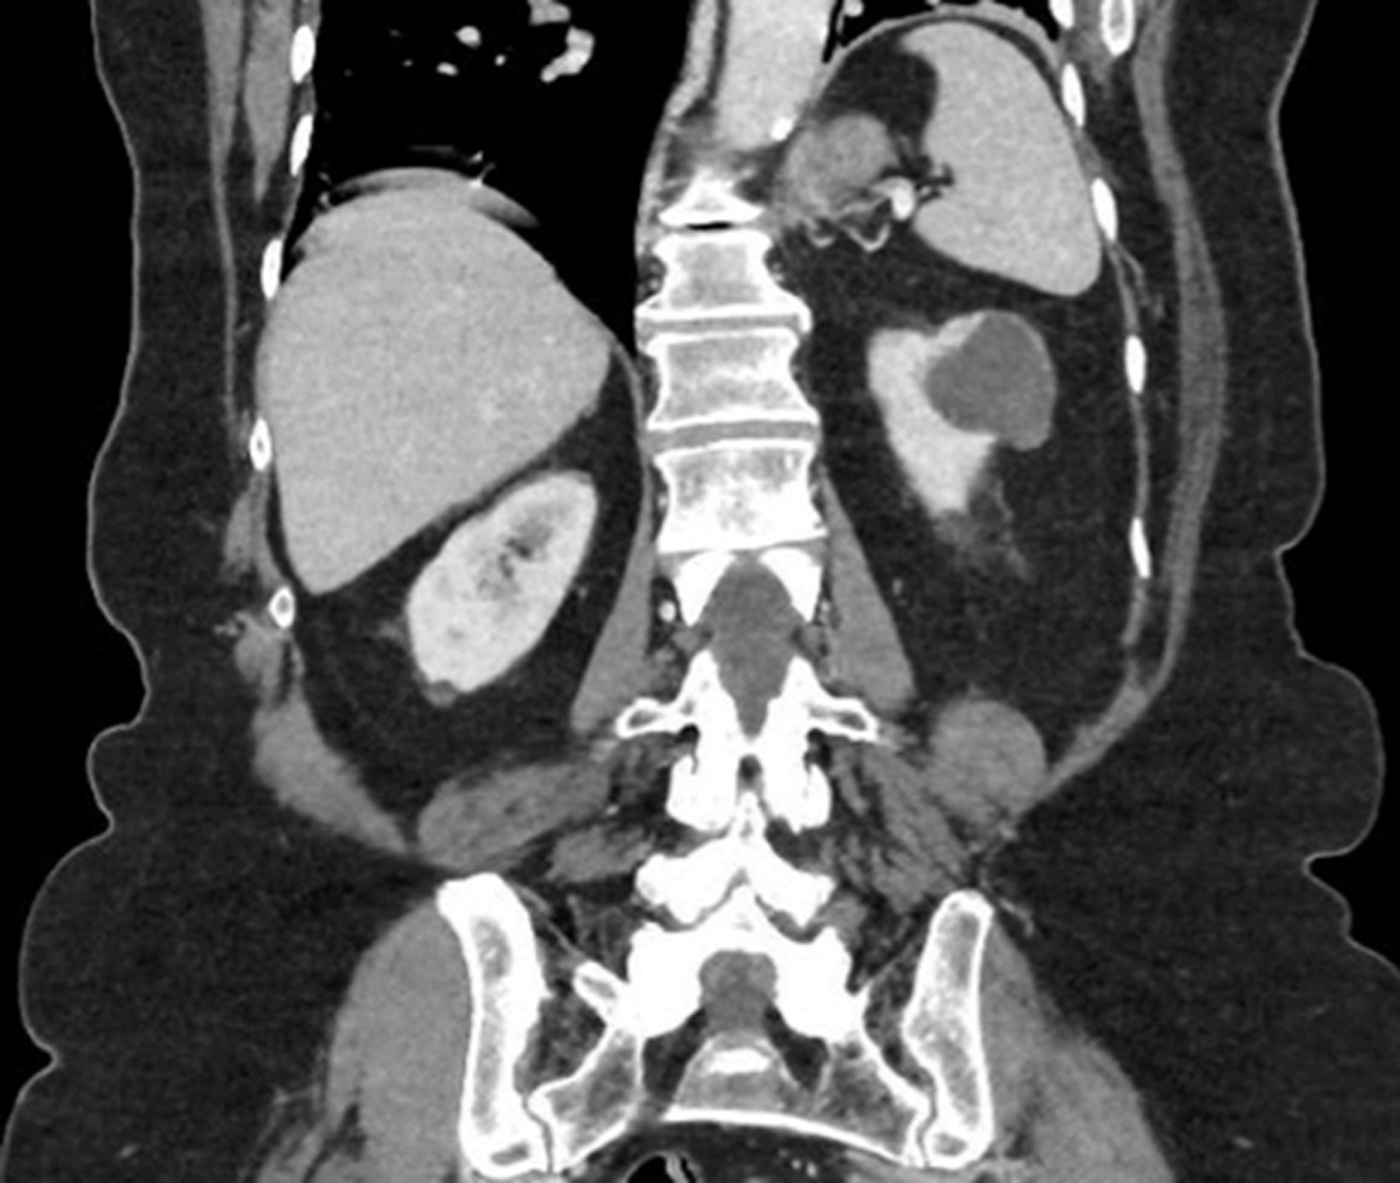

Case 2

A 65-year-old gentleman presented with visible haematuria and underwent the below CT scan. He has hypertension and hyperthyroidism.

Figure 2.

Figure 3.

1. CT renal consists of multiple phases as outlined below [8]: Non-contrast phase - This is conducted prior to intravenous (IV) contrast administration, with the purpose of detecting calcifications (e.g., renal or ureteric stones) and identifying fat content in mass lesions (e.g., AML). It is also useful in having a baseline attenuation with which to compare the contrast images.Corticomedullary phase - This is conducted approximately 25-40 seconds after contrast injection. Its purpose is to highlight renal arteries, cortex and medulla (the renal cortex enhances preferentially). It is useful in assessing vascular anatomy which can aid surgical planning, and in demonstrating renal artery stenosis / arteriovenous malformations and other abnormalities. It can identify early enhancement in hypervascular tumours.Nephrogenic phase - This is conducted approximately 80-120 seconds after contrast injection. It allows both enhancement of the cortex and medulla and is the best phase for detecting renal masses.

2. This is a 5cm, exophytic, cystic, superior pole tumour of the left kidney, stage T1b N0 Mx.